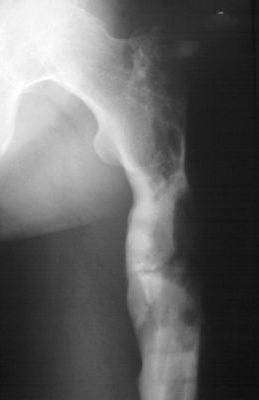

Уважаемые коллеги! Выношу на обсуждение клинический случай. Пациент 38 лет, оперирован дважды. В настоящее время рефрактура. Подробности из анамнеза: в 2007 году пациенту выполнена операция остеосинтез бедренной кости по поводу многооскольчатого перелома с применением пластинки с ограниченным контактом (имплантов с угловой стабильностью и блокируемых гвоздей на момент операции в наличии не было - это, чтобы не обсуждать лишние вопросы). Через 6,5 месяцев после остеосинтеза развился остеомиелит в верхней трети диафиза бедренной кости с образованием секвестра размерами 55х30х25 мм. В 2008 году (через 8 месяцев после остеосинтеза) выполнена вторая операция - удаление металлоконструкции и секвестрэктомия. При удалении пластинки и ревизии ложа секвестра, костная мозоль на сросшемся участке состоятельна. было принято решение заполнить секвестральную полость мышечным лоскутом. В послеоперационном периоде нагрузка на конечность была исключена 2,5 месяца, дополнительная фиксация индивидуальным брейсом. Свищи зажили, обострения остемиелита купировано. Пациент приступил к профессиональной деятельности (автослесарь). В конце ноября при уборке снега произвел резкую опорную нагрузку на конечность, после чего появились умеренные боли нарастающие в течение месяца. В настоящее время госптализирован для оперативного лечения по поводу рефрактуры на уровне верхней трети бедренной кости. Планируется остеосинтез аппаратом Илизарова с стержневой модификации (без обширного вмешательства в зоне перелома)и как вариант тунеллизации через зону перелома с возможным введением в каналы "КоллапАнна", "Сhronos" и.т.п. Также были предложены варианты пластинками с угловой стабильностью, блокируемый остеосинтез гвоздями. Движения в коленном суставе до повторного перелома (сгибание 90 градусов, разгибание 180). Пациент пониженного питания. Какие есть мнения по решению данного случая, может кто-то сталкивался с подобными вариантами развития событий. Всем заранее благодарен за Ваше время. Михаил.

Мне кажется, такой диагноз не отражает всей проблемы. Тут есть и значительный краевой дефект.

А вот гвоздь здесь был бы в самый раз. В качестве "эндопротеза диафиза" он как раз прослужит несколько лет, это намного практичнее аппарата внешней фиксации. И не надо делать никаких пластик и вообще вмешиваться открыто в зоне дефекта.